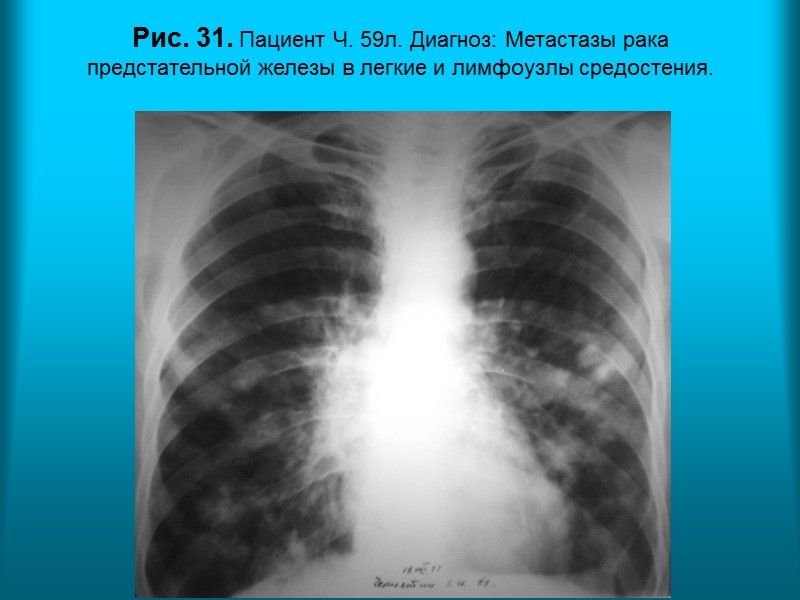

Н.С. Воротынцева. С.С. Гольев Рентгенопульмонология Рис. 31. Пациент Ч. 59л. Диагноз: Метастазы рака предстательной железы в легкие и лимфоузлы средостения.